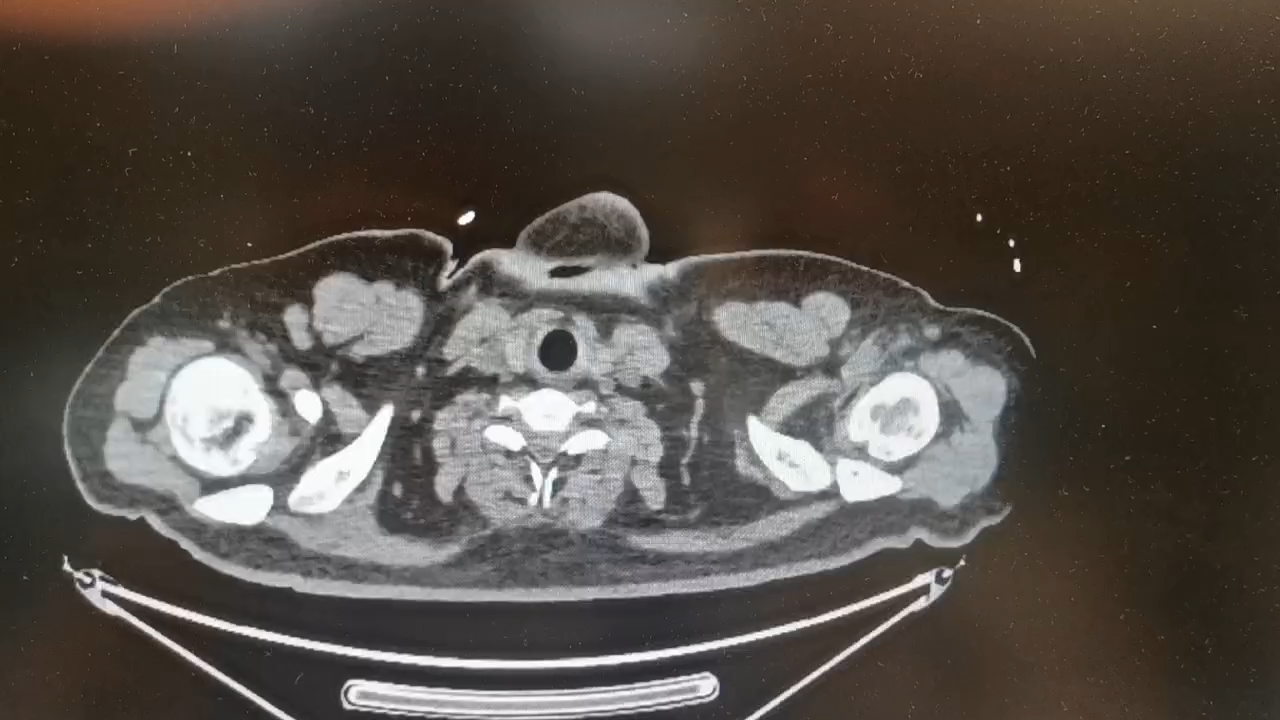

患者入院前12天无明显诱因出现腹泻,稀水样棕褐色大便,4-6次/天,伴乏力,无腹痛、恶心、呕吐,无胸痛、胸闷、憋喘,无发热、咳嗽、咳痰,未行治疗。1天前其同事发现患者没上班、电话不接,遂到宿舍发现其意识模糊,可叫醒,体温:40℃,有大小便失禁,无呕吐,就诊于当地医院行胸腹CT检查:双肺炎症,心腔内低密度灶,脂肪肝,部分肠管扩张并气液平(片子就表现为心衰肺门周围阴影);血常规:血红蛋白43g/L,PCT:2.5ng/ml,总胆红素:47.8umol/L。给予退热、补液等治疗,患者家属为进一步治疗当天转入我院急诊,复查血常规:血红蛋白:42,血小板:121,前降钙素:3.2ng/ml,N端脑钠肽前体:1165pg/ml,D-二聚体:1.5,高敏肌钙蛋白I:686.74ng/L,总胆红素:52umol/L,未结合胆红素:29umol/L。给予纠正心衰、抗感染等治疗后,转入科室。

06-28患者已无任何不适,可以出去做检查了,去复查胸腹CT:

带着病人回病房后,一看片子,影像科老师说,捋了一遍没找到破口,再领着病人回CT室扫个盆部吧!